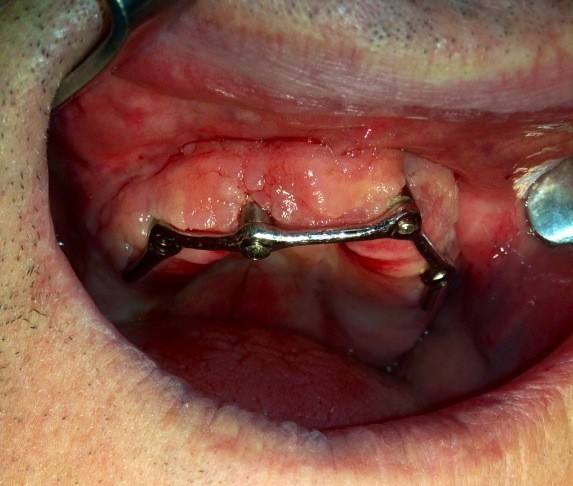

IMPLANTOLOGIA A CARICO IMMEDIATO.RIPRISTINO ESTETICO E FUNZIONALE IN 24h

RIABILITA LA TUA BOCCA IN 2 GIORNI!

Impianti dentali faccette estetiche e denti fissi! guarda questo caso eseguito in 2 giorni